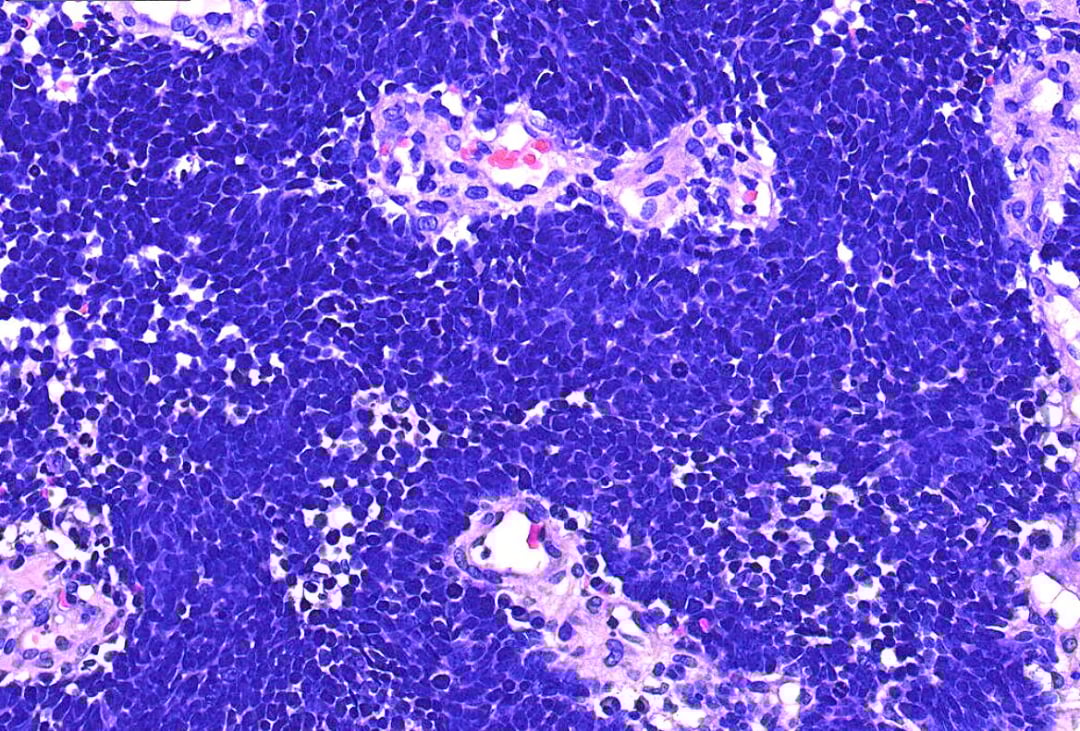

高倍镜下,肿瘤细胞胞质稀少,核染色深,核仁不明显,核分裂象多见。